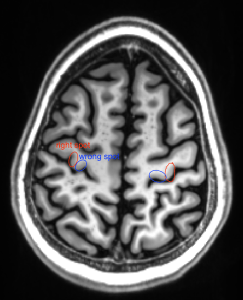

The position within the axial slice is super easy in about 80% of the people. There, however, few people where its not so clear. In those cases, I found it helpful to project the superior frontal sulcus further back. If there is no sulcus in this direction, there is a high likelihood that the selected “omega” structure is actually in the sensory cortex. The superior frontal sulcus is located anterior of the motor cortex. It goes along the anterior-posterior direction and is depicted in green in the examples below.

Below are some examples of how the “omega” structure alone can be misleading. Having the superior frontal sulcus as reference helps. The wrong spots can be identified because they don’t have the superior frontal sulcus anterior to them. Of course, it is helpful to go through many slices to spot the superior frontal sulcus.